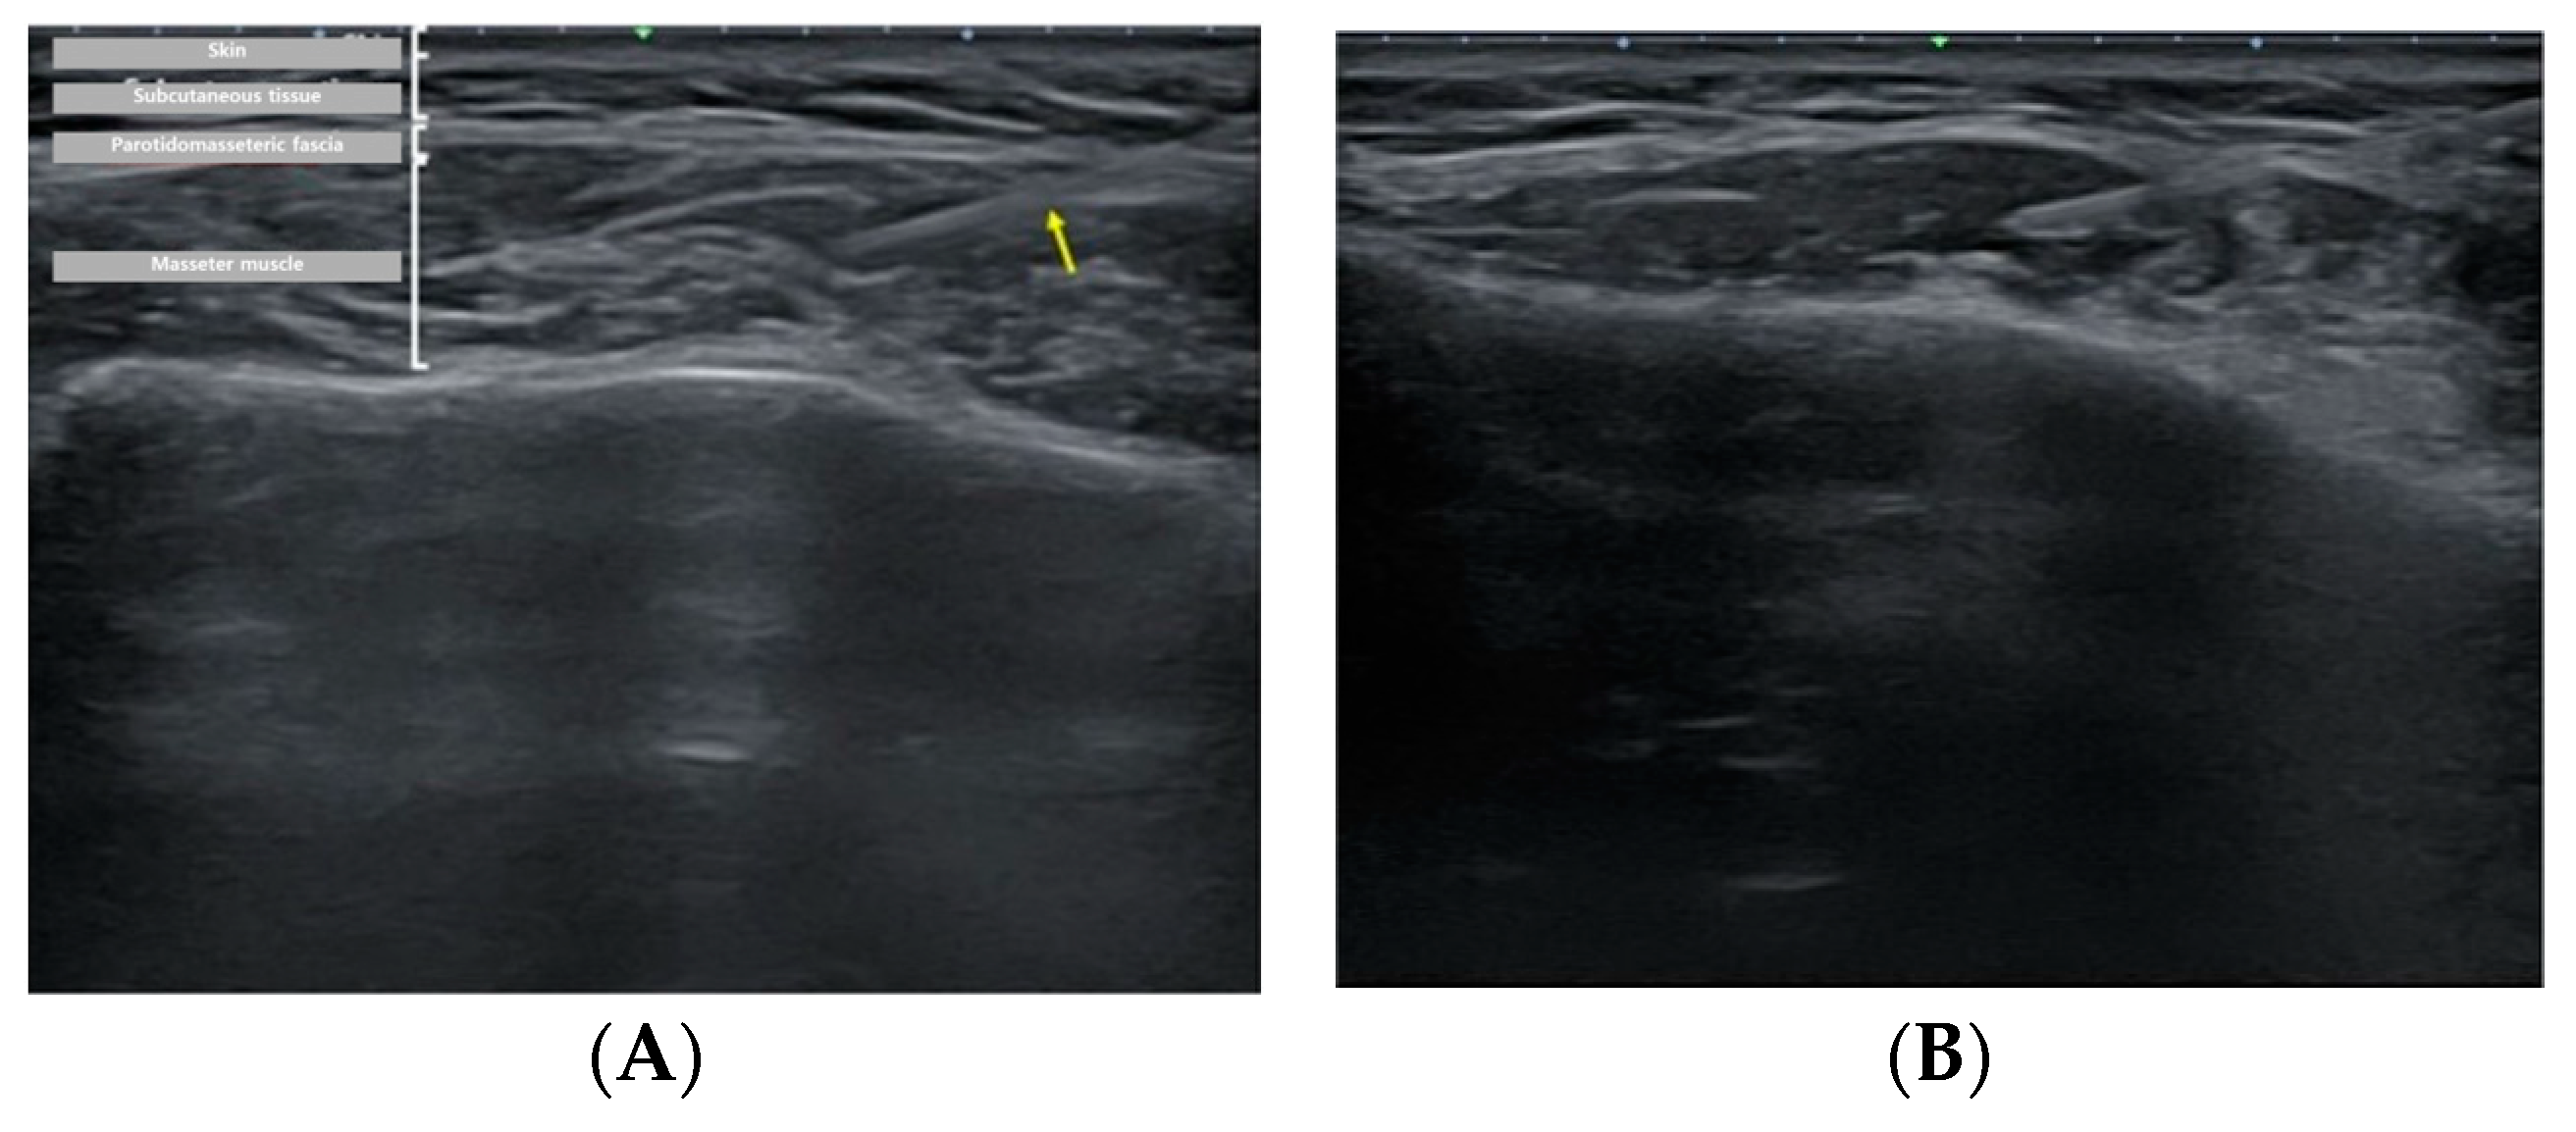

Figure 3. Ultrasound (US)-guided BoNT-A injection. With the US system set to B-mode, the thickest region was identified, and injections were administered in that specific area. Real-time monitoring using US confirmed the accurate delivery of injections.

Figure 4. Ultrasound image showing injection dynamics after BoNT-A injection. (A) The yellow arrow notes the BoNT-A injection needle. Puncture was performed using a 1-cc syringe, with injection into the thickest region of the masseter muscle. (B) Immediate post-injection view.

The patient, who had previously received Botox injections in one masseter muscle using the landmark-guided, three-point injection technique, underwent injections on the opposite side of the face using the US-guided, single-point injection approach. Following the previously described method for masseter muscle assessment, the thickest region was identified using US B-mode, and its thickness (mm) was measured (Figure 2). Subsequently, with the US probe fixed in place, the injection needle was carefully guided into the muscle, ensuring proper and effective administration of the injection (Figure 3). Once it was confirmed that the injection was appropriately delivered at the thickest part of the muscle, the needle angle was adjusted to approximately 30 degrees in a thread-like manner to ensure even distribution of the drug throughout the remaining muscle parts (Figure 4). The needle was then withdrawn. The injection dosage remained consistent with the side that underwent landmark-guided, three-point injection.